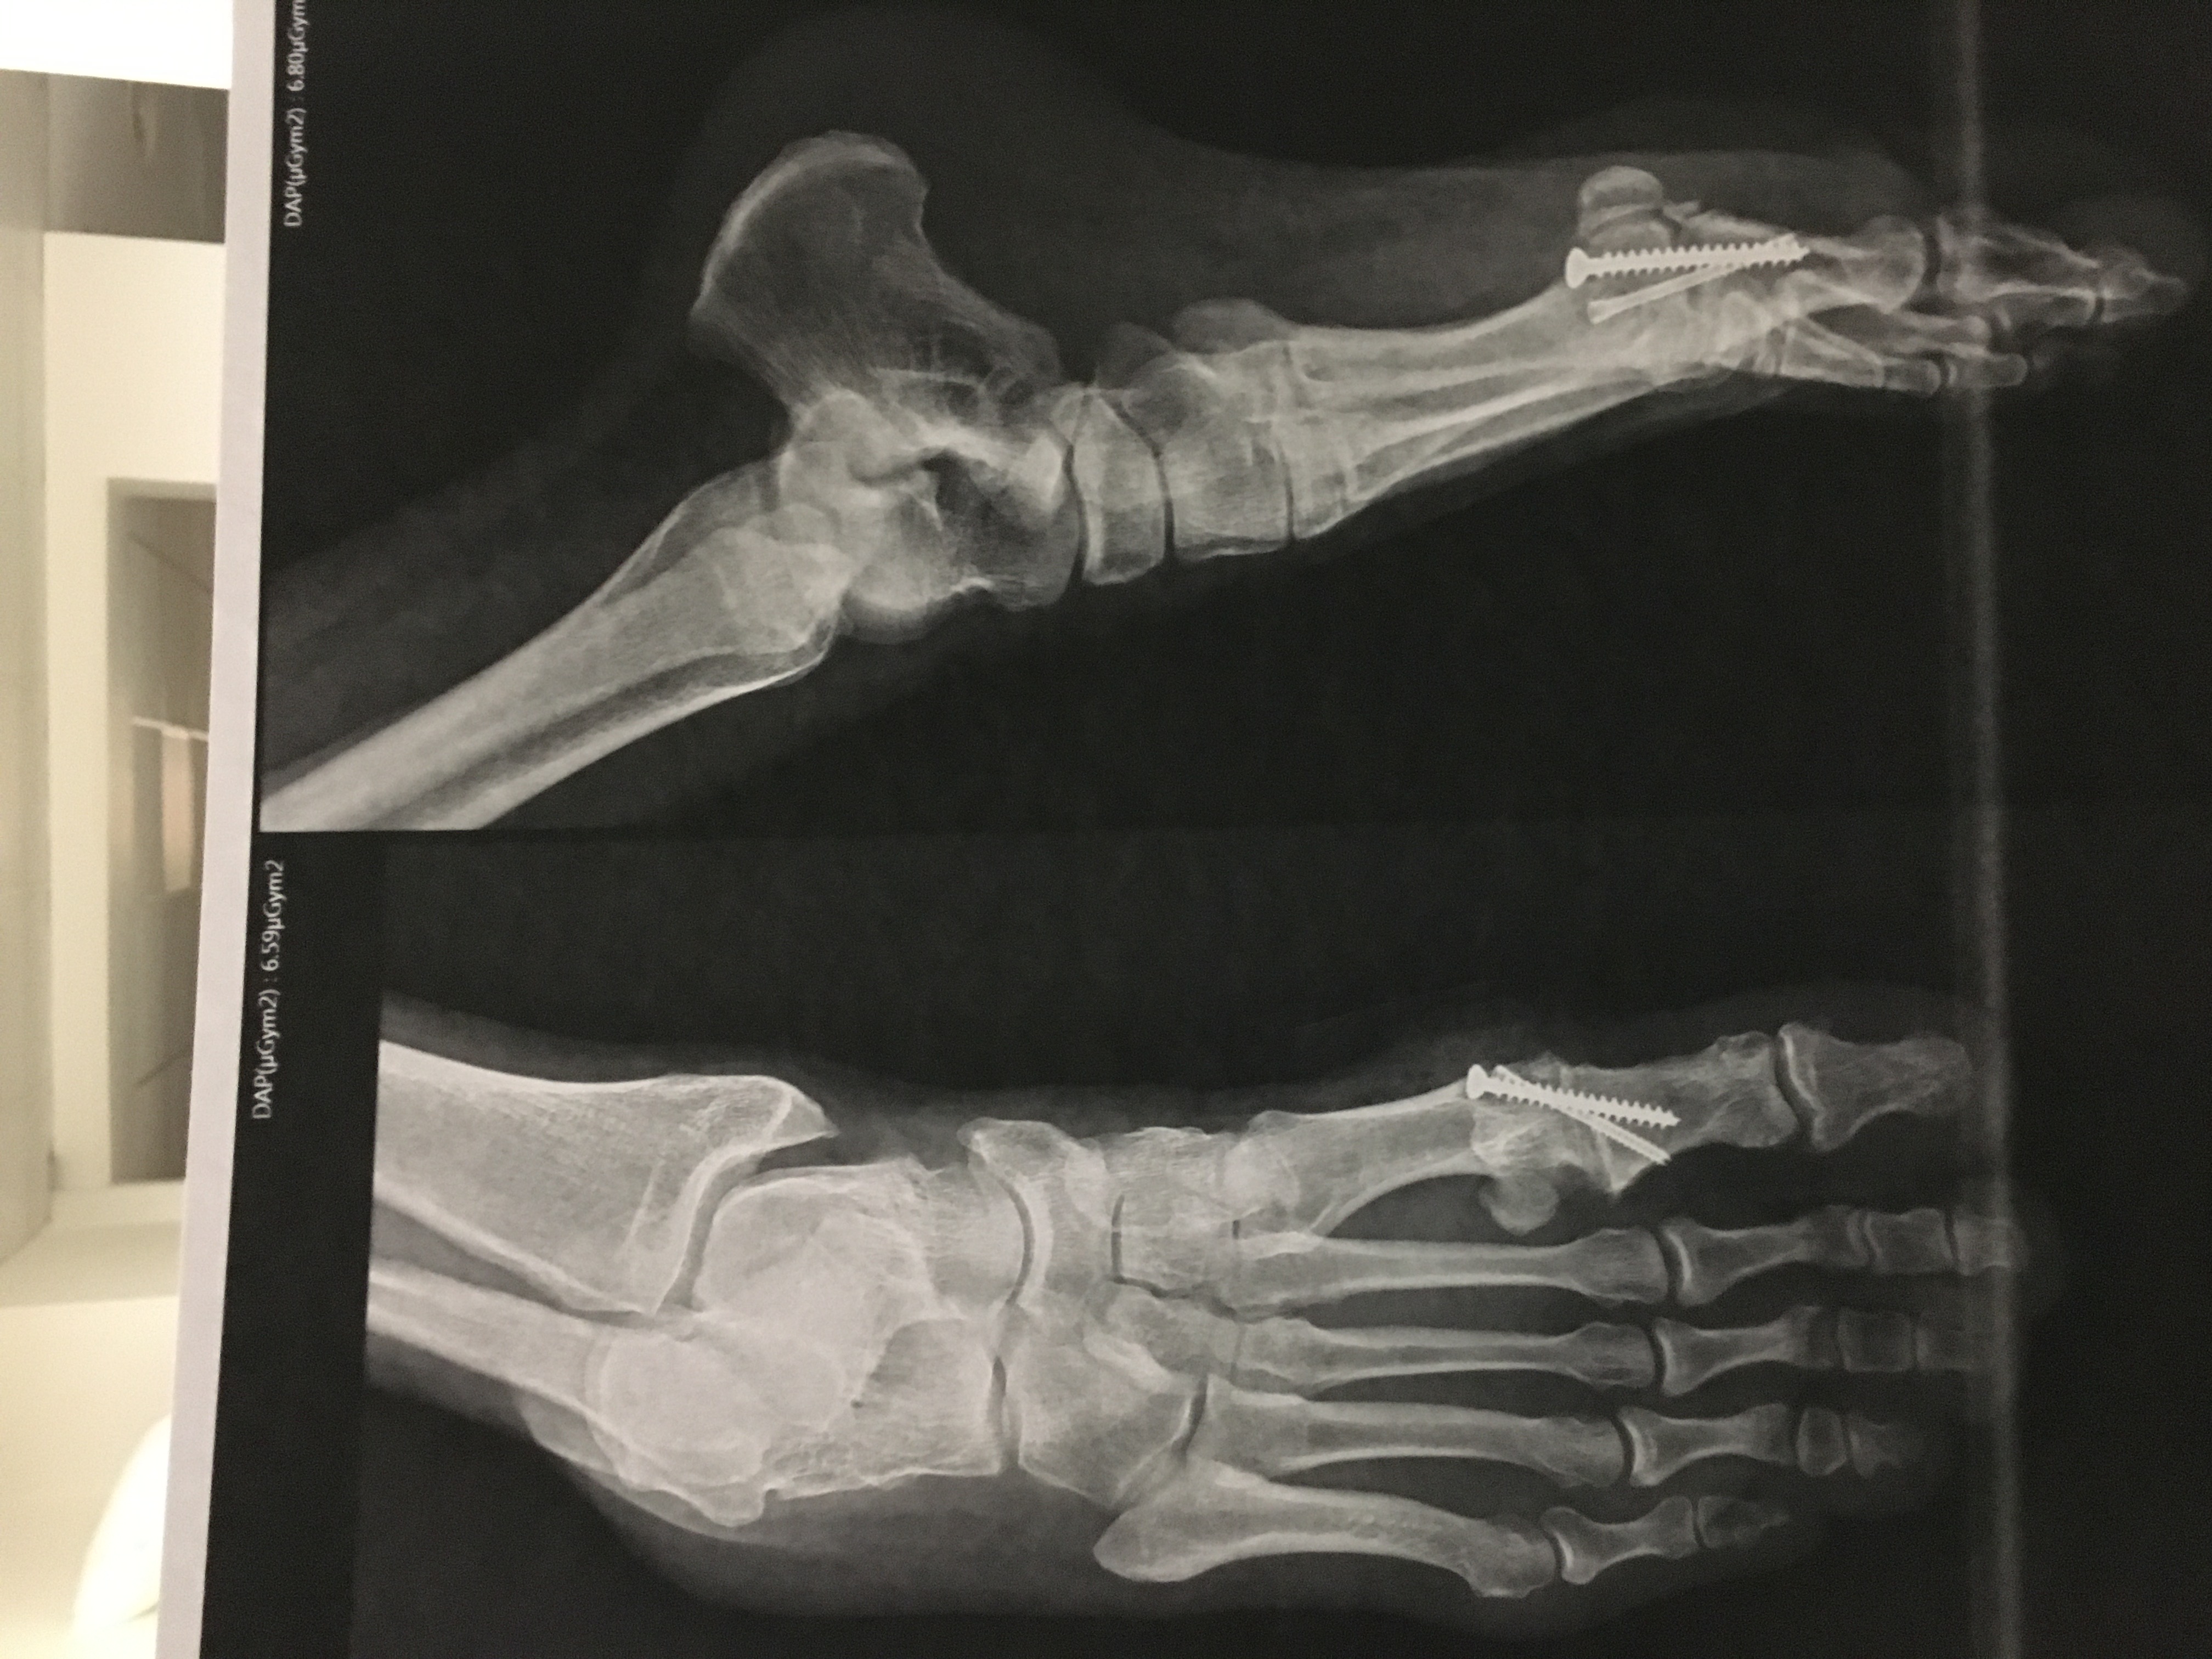

Moi aussi révision du pied droit !!!

Mais comment tu t'es mis une vis à bois dans le pied ?

Apparemment ça fait partie de l'opération

(arthrodèse par vis pour maintenir l'écart des os et garder plus longtemps de la mobilité)

Mais ça se soigne pas avec une vis à bois ça !!